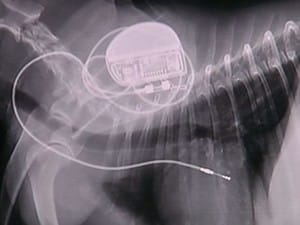

A cirurgia da Joana reuniu um grande time de veterinários. No exame de raio-X é possível ver o marca-passo, do mesmo tipo usado em seres humanos. “Para o cão não muda nada. A implantação do aparelho tem indicação em animais que têm essa doença, a síndrome do nódulo doente, animais que têm bloquei atrioventricular, em que o impulso elétrico para despolarizar o coração não passa do átrio para o ventrículo”, explica a veterinária Maria Lúcia Gomes.